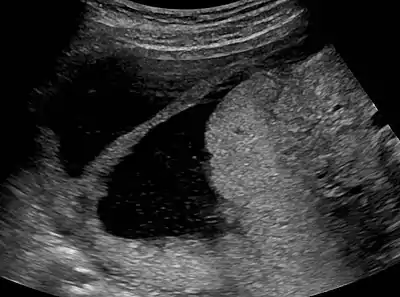

![]() | |

| Ultrasound view. | |

The history of a pregnancy event followed by a D&C leading to secondary amenorrhea or hypomenorrhea is typical. Hysteroscopy is the gold standard for diagnosis.[13] Imaging by sonohysterography or hysterosalpingography will reveal the extent of the scar formation. Ultrasound is not a reliable method of diagnosing Asherman's Syndrome. Hormone studies show normal levels consistent with reproductive function.